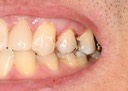

Scott Kanamori #12 pre-op